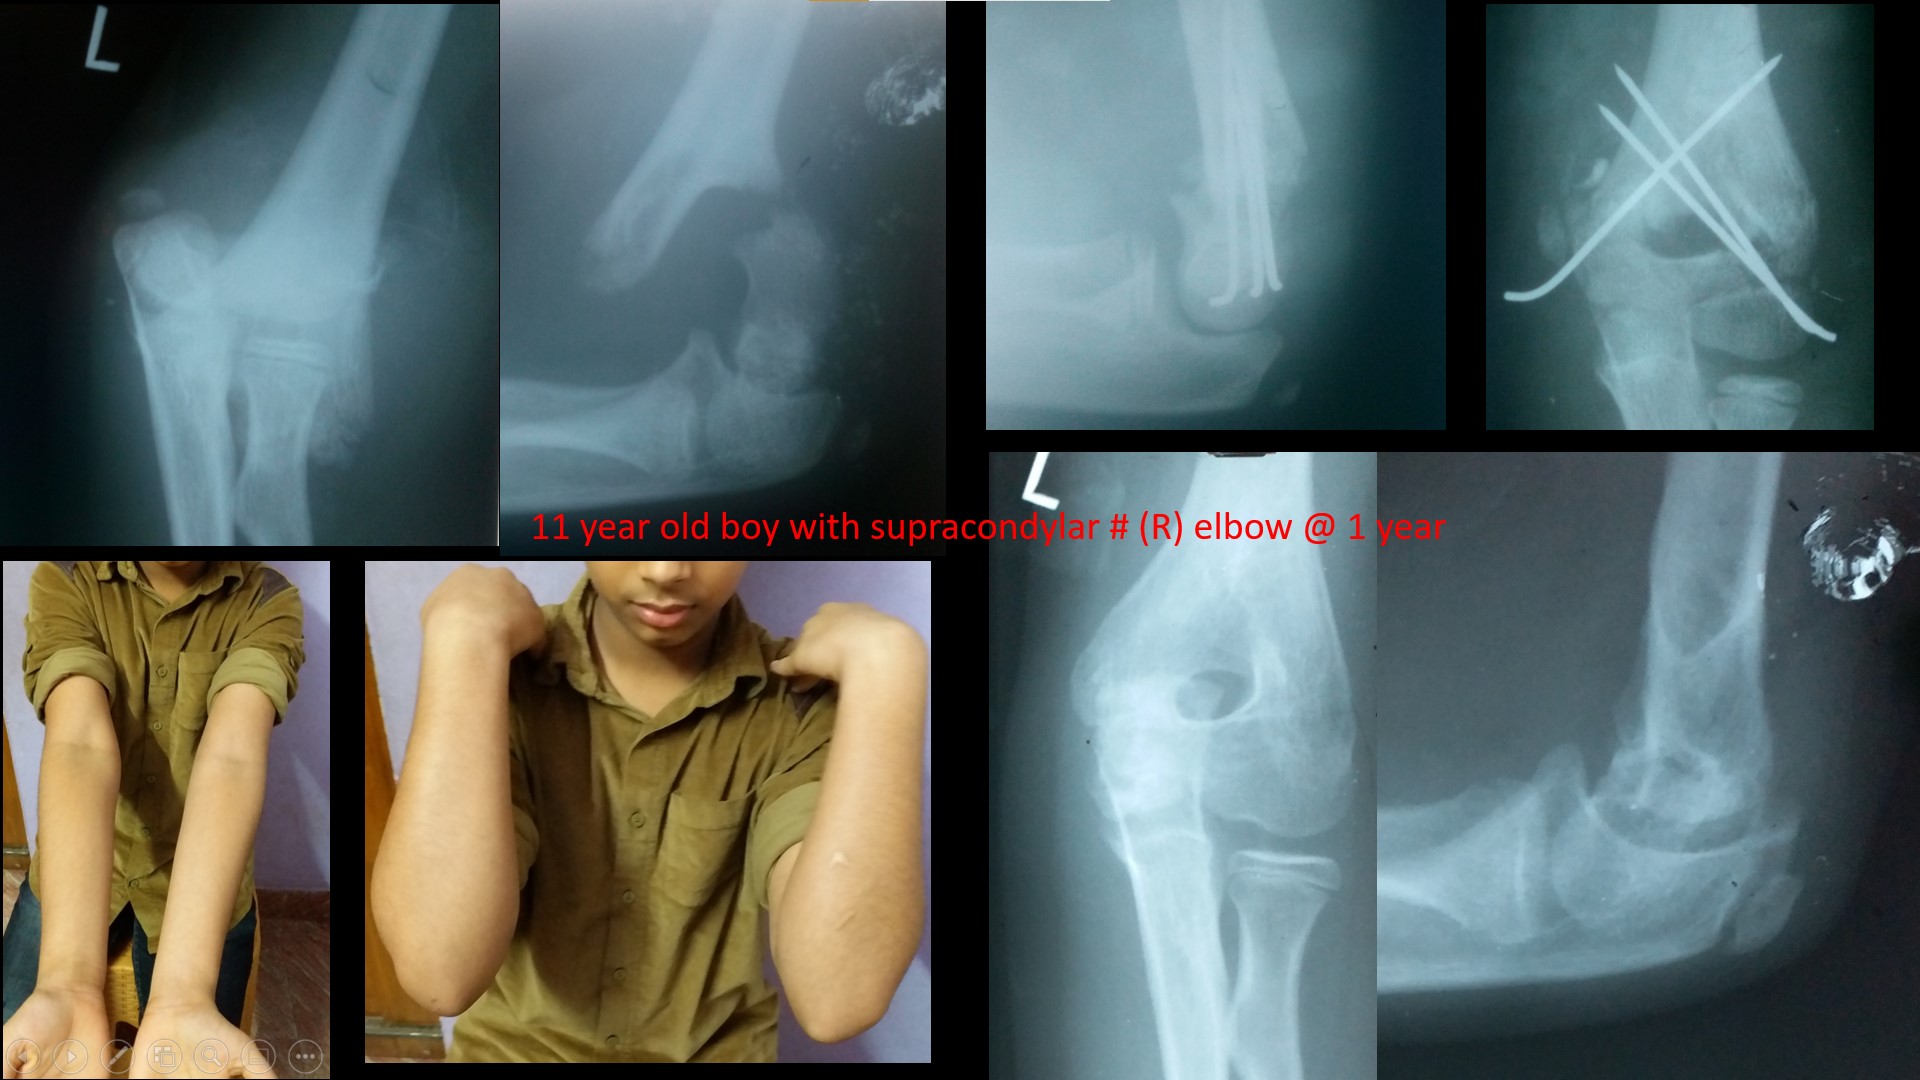

SUPRACONDYLAR #